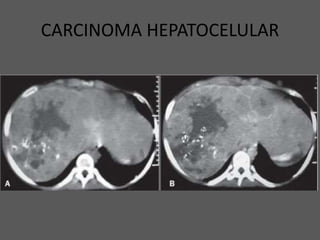

CARCINOMA HEPATOCELULAR